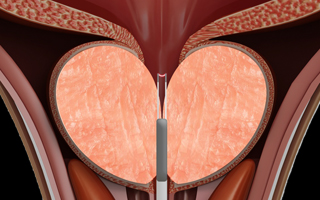

플라즈마 장치를 요도를 통해 삽입합니다.

-

02

2단계

플라즈마를 활성화 상태로 후방으로 이동하고, 비활성화 상태로 전방으로 이동하며 조직을 제거 합니다.